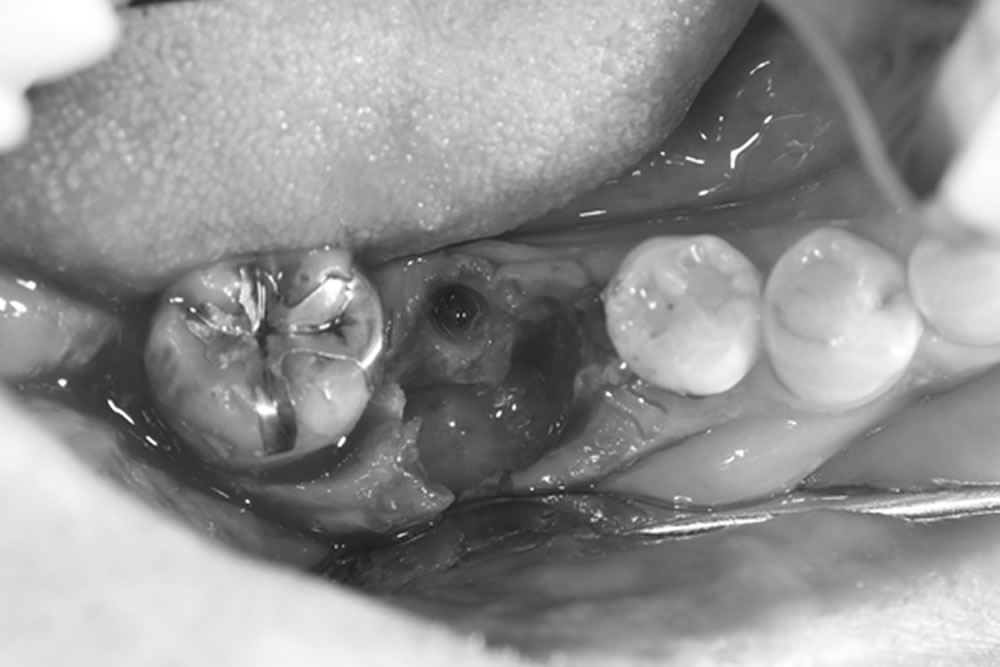

インプラント埋入手術の実施

- 11.1 インプラント埋入手術の実施

- 11.2 ①術前

- 11.3 ②歯肉を切開

- 11.4 ③インプラントを埋入

- 11.5 ④骨造成の実施

- 11.6 ⑤患部の保護